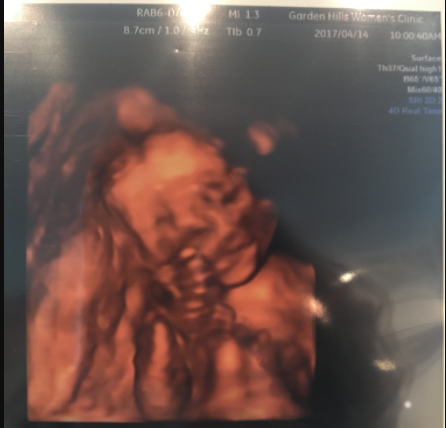

20週0日(20w0d・男の子)|saori 0104 さん

エコー写真撮影時のエピソード:

安定期に入った時に新居に引越しをし、病院を変えました。その時、初めての妊婦健診が胎児スクリーニングの時でした。胎児スクリーニングでは3Dエコーが見られるということで、初めての3Dエコーに私も主人も大興奮でした。助産師さんからは「この時期はみんな買おが一緒ですよ」と言われましたが、「このほっぺたが主人に似てる!」「鼻は私に似てるよね!」などと助産師さんお構いなしに盛り上がってしまったのはいい想い出です。

先程も記載した通り安定期に入った20週の頃にエコーを撮りましたが、私は妊娠悪阻で会社を1ヶ月半休職し、この頃は復帰して1ヶ月程たったときでした。今思うと1番体が動きやすく仕事もバリバリとやっていましたが、貧血が酷く電車の中で倒れることもしばしばありました。主人にはその度心配をかけさせてしまい、私の体調をすごく気にかけてくれました。健診には毎回ついてきてくれるので、一緒に赤ちゃんが産まれてきてくれることを楽しみにしてくれているんだなと感じます。